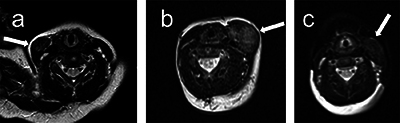

Results: We found that FC presents a T1 signal isointense to the muscle, a T2 signal hyperintense to the muscle, a variable diffusion signal and a thick enhancing peripheral ring after contrast administration.

Abstract Image